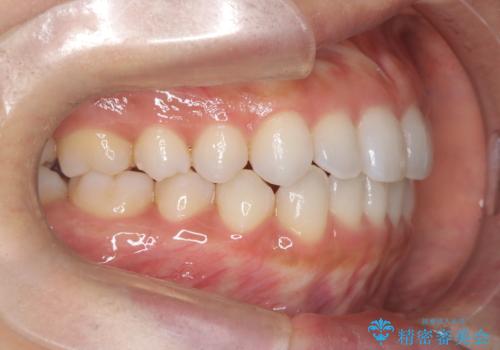

前歯の叢生を非抜歯で改善|インビザライン+IPR・遠心移動・FIX保定

- 前歯部のガタガタ(叢生)を非抜歯で改善するため、インビザラインによるマウスピース矯正を計画しました。抜歯は行わず、歯間をわずかに削るIPR(ディスキング)と奥歯を後方に移動させる遠心移動を併用して、歯を並べるスペースを確保します。歯列が整った後は、FIXリテーナー(固定式保定装置)で後戻りを防止し、安定した歯並びを維持します。

歯を抜きたくないというご希望に応え、インビザラインを用いて非抜歯で歯列を整えました。前歯に必要なスペースを確保するため、歯間をわずかに削るIPRと奥歯を後方に移動する遠心移動を組み合わせました。これにより自然で美しい歯並びを実現。治療終了後は、歯の裏側に目立たないFIXリテーナーを装着し、歯列の後戻りを効果的に防ぎました。患者様は治療中も審美的にストレスなく過ごされ、満足度の高い結果を得られました。